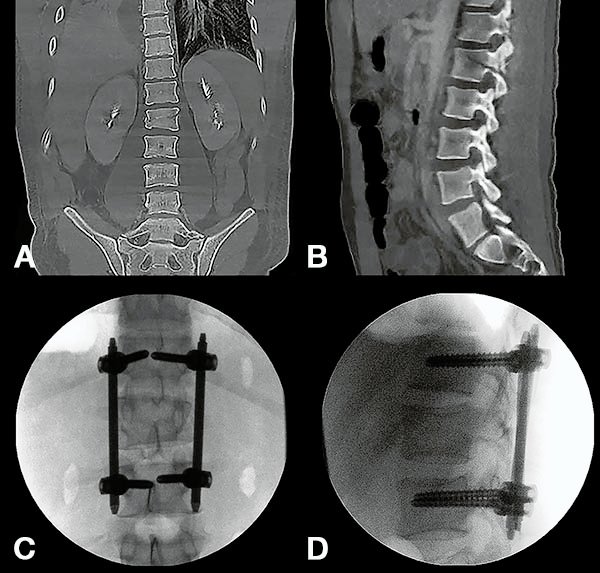

Figura 4:

Caso 8. Hombre de 52 años, accidente vehicular de alta energía cinética. Fractura cerrada de antebrazo, síndrome de distrés respiratorio, hemotórax bilateral, hematocrito en descenso. Se diagnostico una fractura A4 de T8 con mínimo compromiso del canal espinal, posición en cifosis y hemotórax bilateral a predominio izquierdo.

Figura 5:

Caso 8. Se realizó una estabilización percutánea T6-T10. El paciente retornó a UTI, para estabilizar su cuadro respiratorio y hemodinámico.

Figura 6:

Caso 8. A la semana de la primer cirugía el paciente se encontraba en condiciones y se realizó la corpectomía por via lateral MIS.

Figura 7:

Caso 8. Control postoperatorio alejado del paciente con un buen callo de fusión, sin pérdida de corrección.